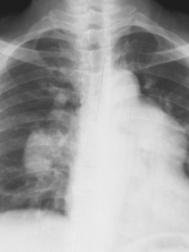

肺动脉高压是一种极度严重的疾病。75%的患者集中于20~40岁年龄段,15%的患者年龄在20岁以下。肺动脉高压的症状包括:呼吸短促、易于疲劳、晕厥、胸痛以及腿部和踝部水肿。此外,心脏听诊可闻P2亢进。如果不及时治疗,患者的肺动脉高压会逐步加重,甚至使寿命缩短。多数肺动脉高压相关的症状源自右心衰竭。在上世纪90年代以前,医学界对这种疾病确实缺少治疗手段。但此后一些新的药物陆续被研发出来,患者5年或10年平均生存率可提高数倍。药物之外,基因治疗、活体肺移植、房间隔造瘘等新疗法也不断出现。肺动脉高压分为原发性和继发性两类。